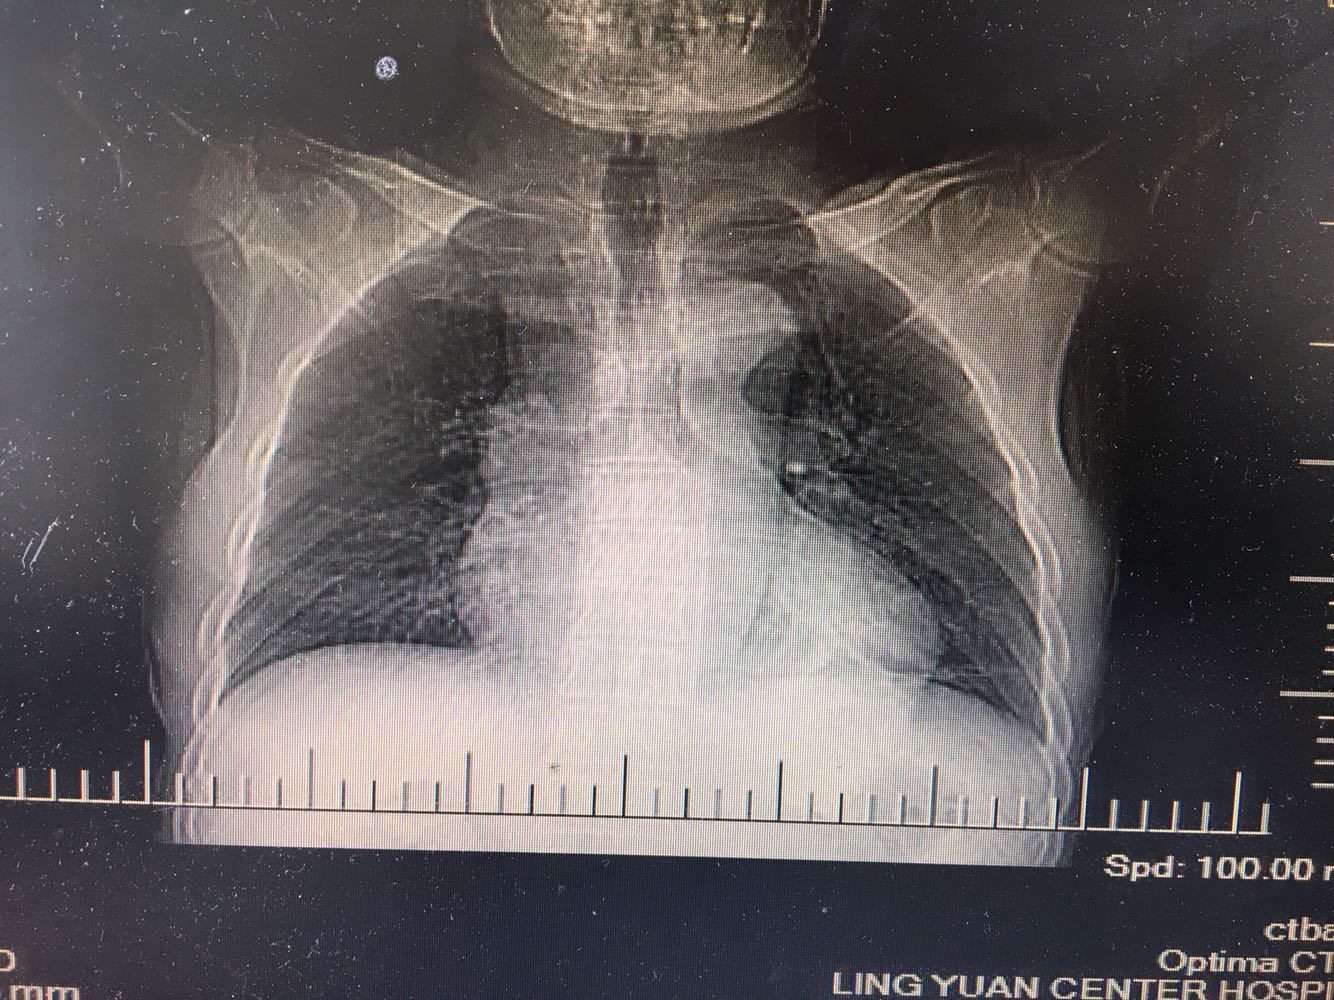

左肺下叶鳞癌

男,63岁,咳嗽1个月入院,患者自述1个月前无诱因咳嗽,阵发性干咳,无痰,时有血丝,无发热,左胸痛,活动后气短,静滴头孢13天无好转,门诊查肺CT后以 肺占位收入我科,病来饮食睡眠可,体重明显下降。既往疝气术后1年,吸烟史30年,每日1包。

左肺癌

左肺中央型肺癌,是否可以手术,还是化疗,放疗,靶向治疗?